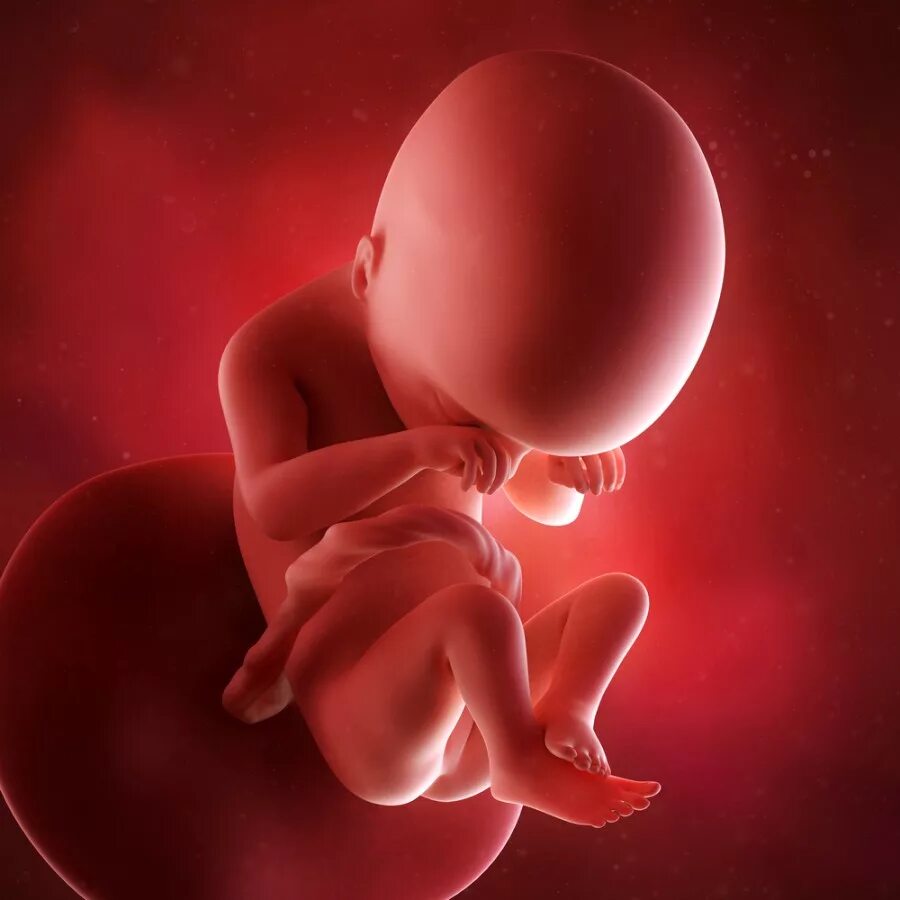

Как выглядит ребенок в 18 недель